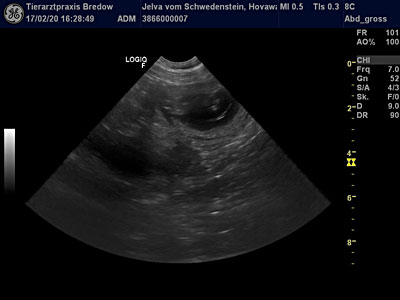

17.02.2020

30. Tag

"Ultraschall" |

Die Ungewissheit hat ein

Ende. Die heutige

Ultraschalluntersuchung bestätigte unsere Vermutung - Jelva ist tragend! Mehrere

Fruchtblasen mit ihren Föten konnten wir sehen - der L-Wurf ist im

Anmarsch. Jelva geht es sehr gut. Sie zeigt sich etwas ruhiger und

anhänglicher als sonst, aber ist wachsam wie eh und je! Sie wog heute beim

Tierarzt 32.2 kg - für Jelva Normalgewicht - also alles im grünen

Bereich.